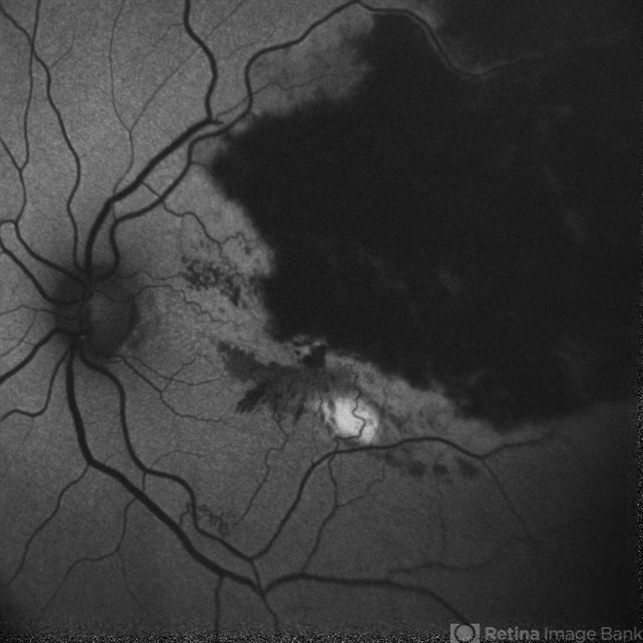

- Autofluorescent Image(G-mode) of a 54 year old male case of LE Branch Retinal Vein Occlusion with Macular Edema.